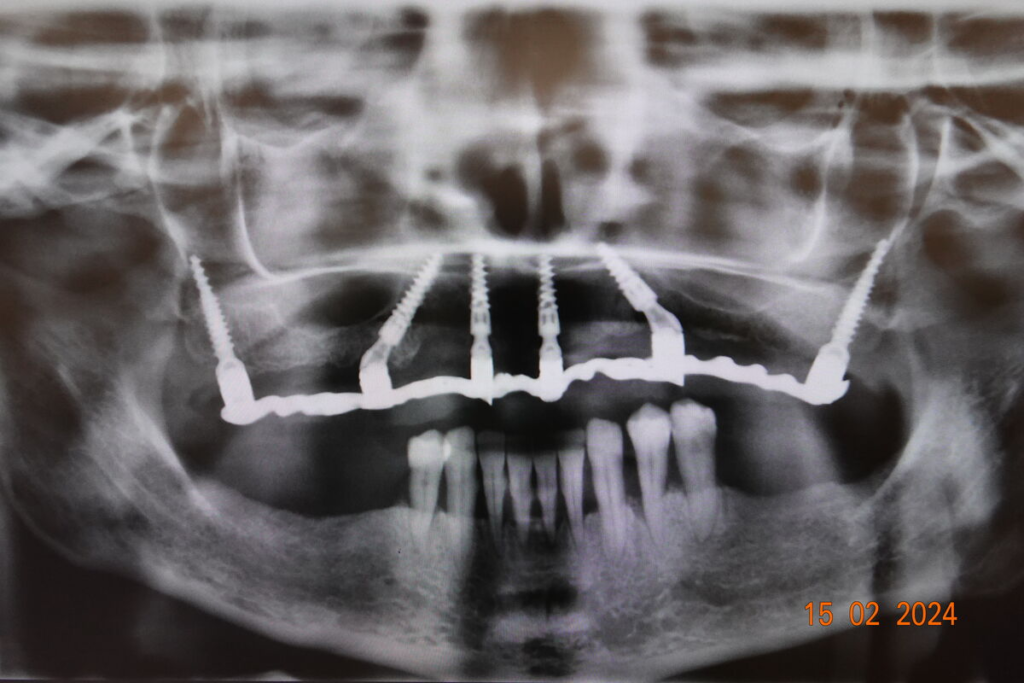

- CBCT 3D snímkování, intraorální skener

- CBCT 3D, vyšetření, fotodokumentace

- 4–6 implantátů metodou All-on-X

Technika All-on-X — I. fáze